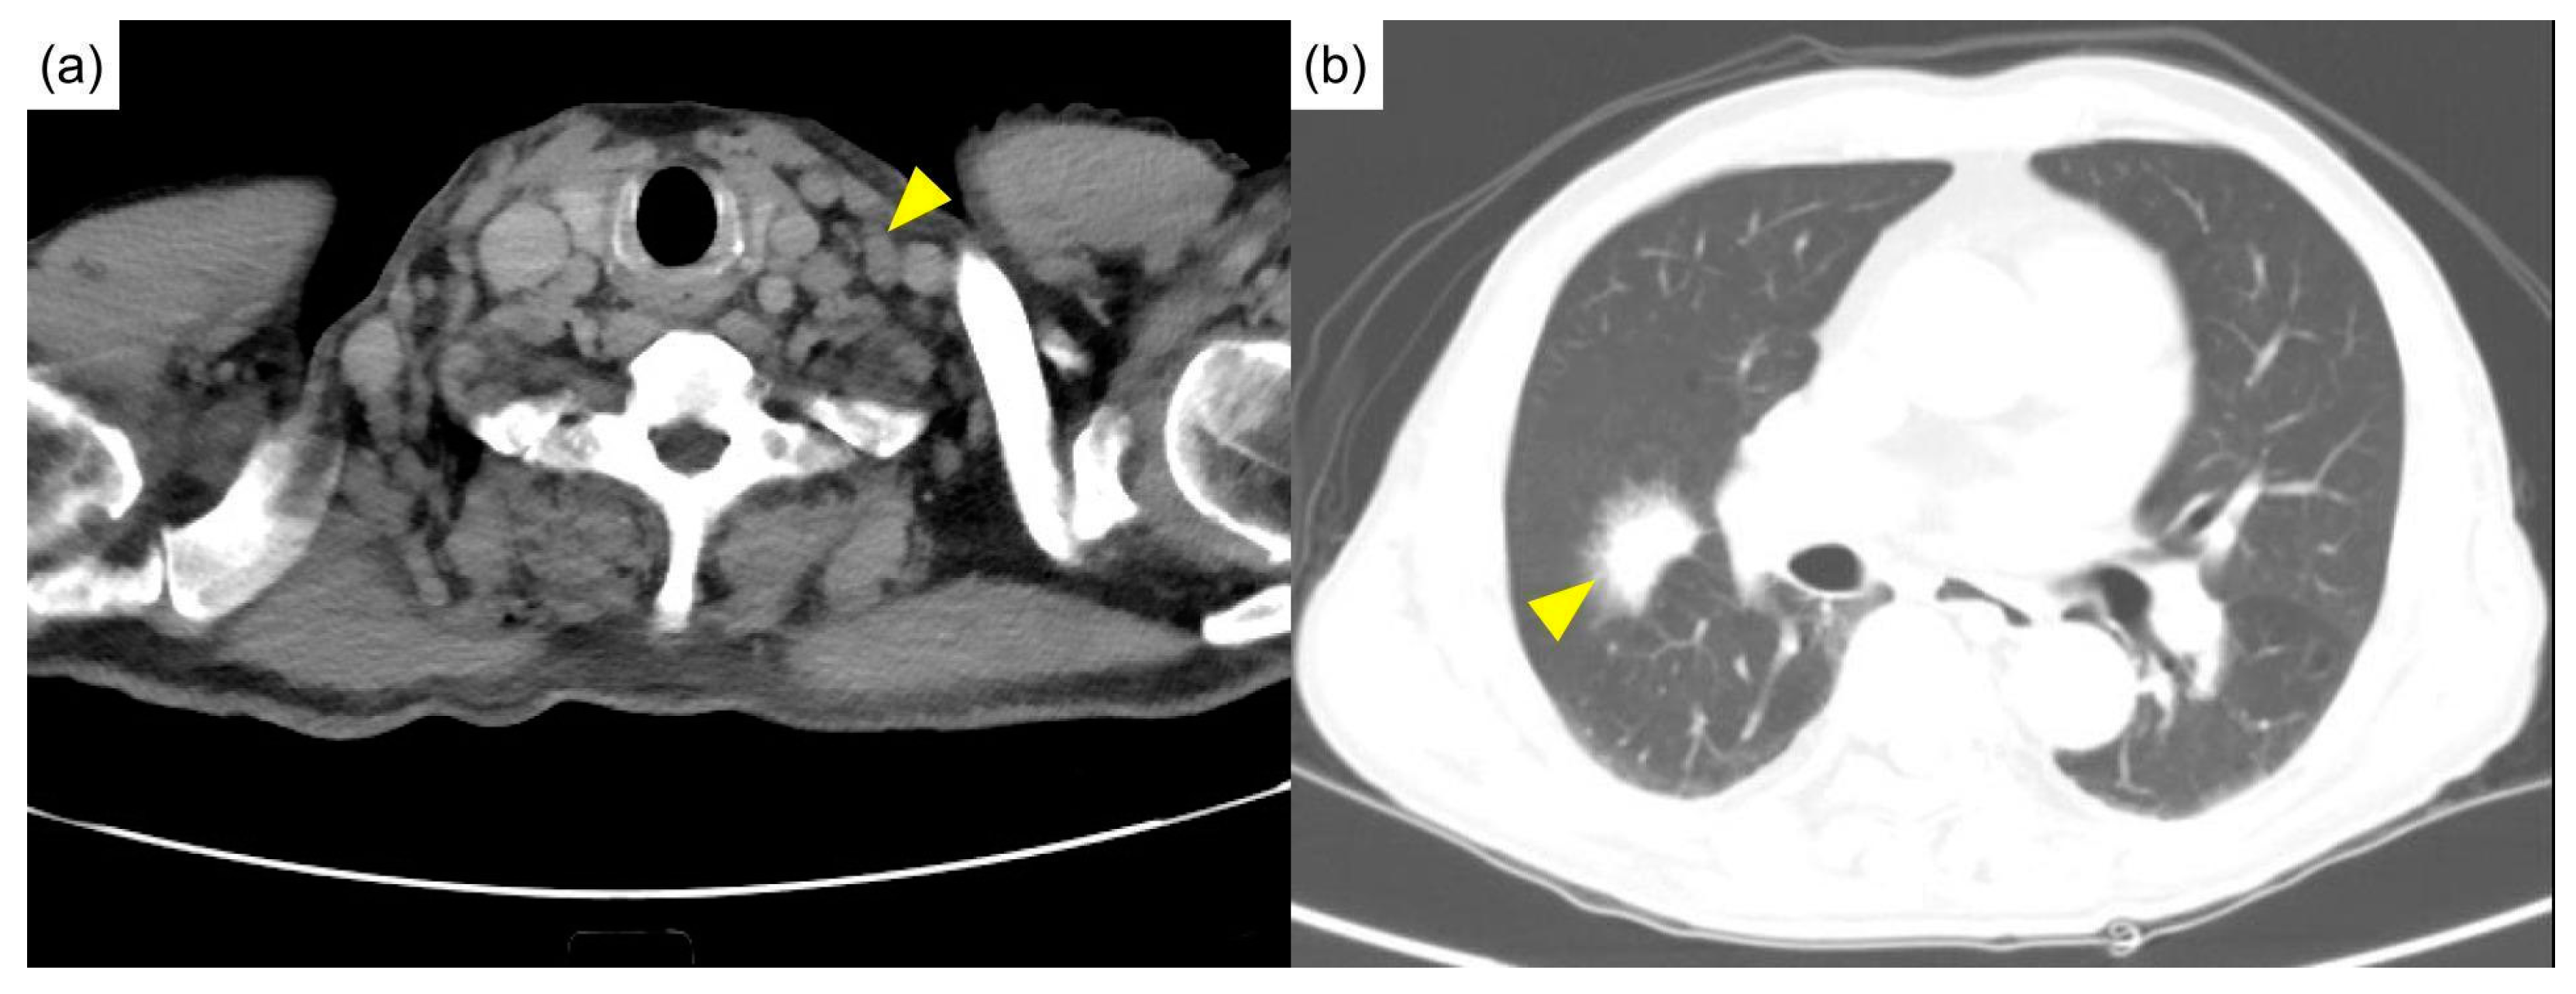

Physical examination showed a pale appearance and multiple lymphadenopathies at the neck and bilateral axilla, without active synovitis or skin lesions. Computed tomography of the head, neck, and chest showed multiple lymphadenopathies over the bilateral neck (Figure 1a) and mediastinum and multifocal ill-defined small patchy opacities over perihilar regions and the right middle lobe of the lung (Figure 1b).

Figure 1.

Initial computed tomography. (a) Diffuse lymphadenopathies (arrowhead) were noted in the neck computed tomography. (b) The chest computed tomography revealed a mass in the right middle lobe of the lung (arrowhead).